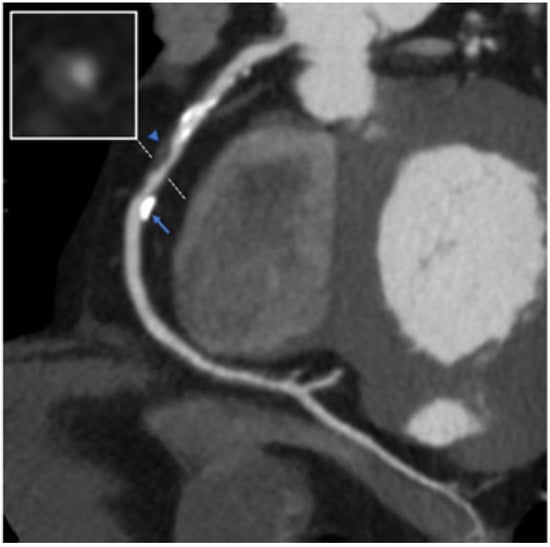

7.3. Coronary Aneurysm